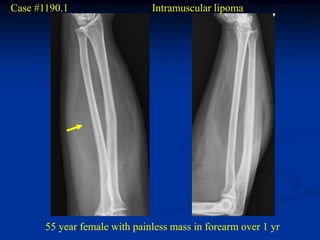

Case #1190.1                   Intramuscular lipoma

55 year female with painless mass in forearm over 1 yr

Sagittal MRI

T-1   T-1              PD-FS   Gad

Axial T-1

Gad

Surgical resection

Case #1190.1 Intramuscular lipoma 55 year female with painless mass in forearm over 1 yr